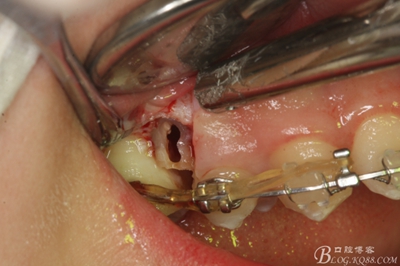

圖14.用小球鉆縱分15牙根

圖15 .微創(chuàng)挺把15牙根縱分成近遠中兩塊

圖16.微創(chuàng)挺挺松近中根面部分,從16與14之間間隙出來